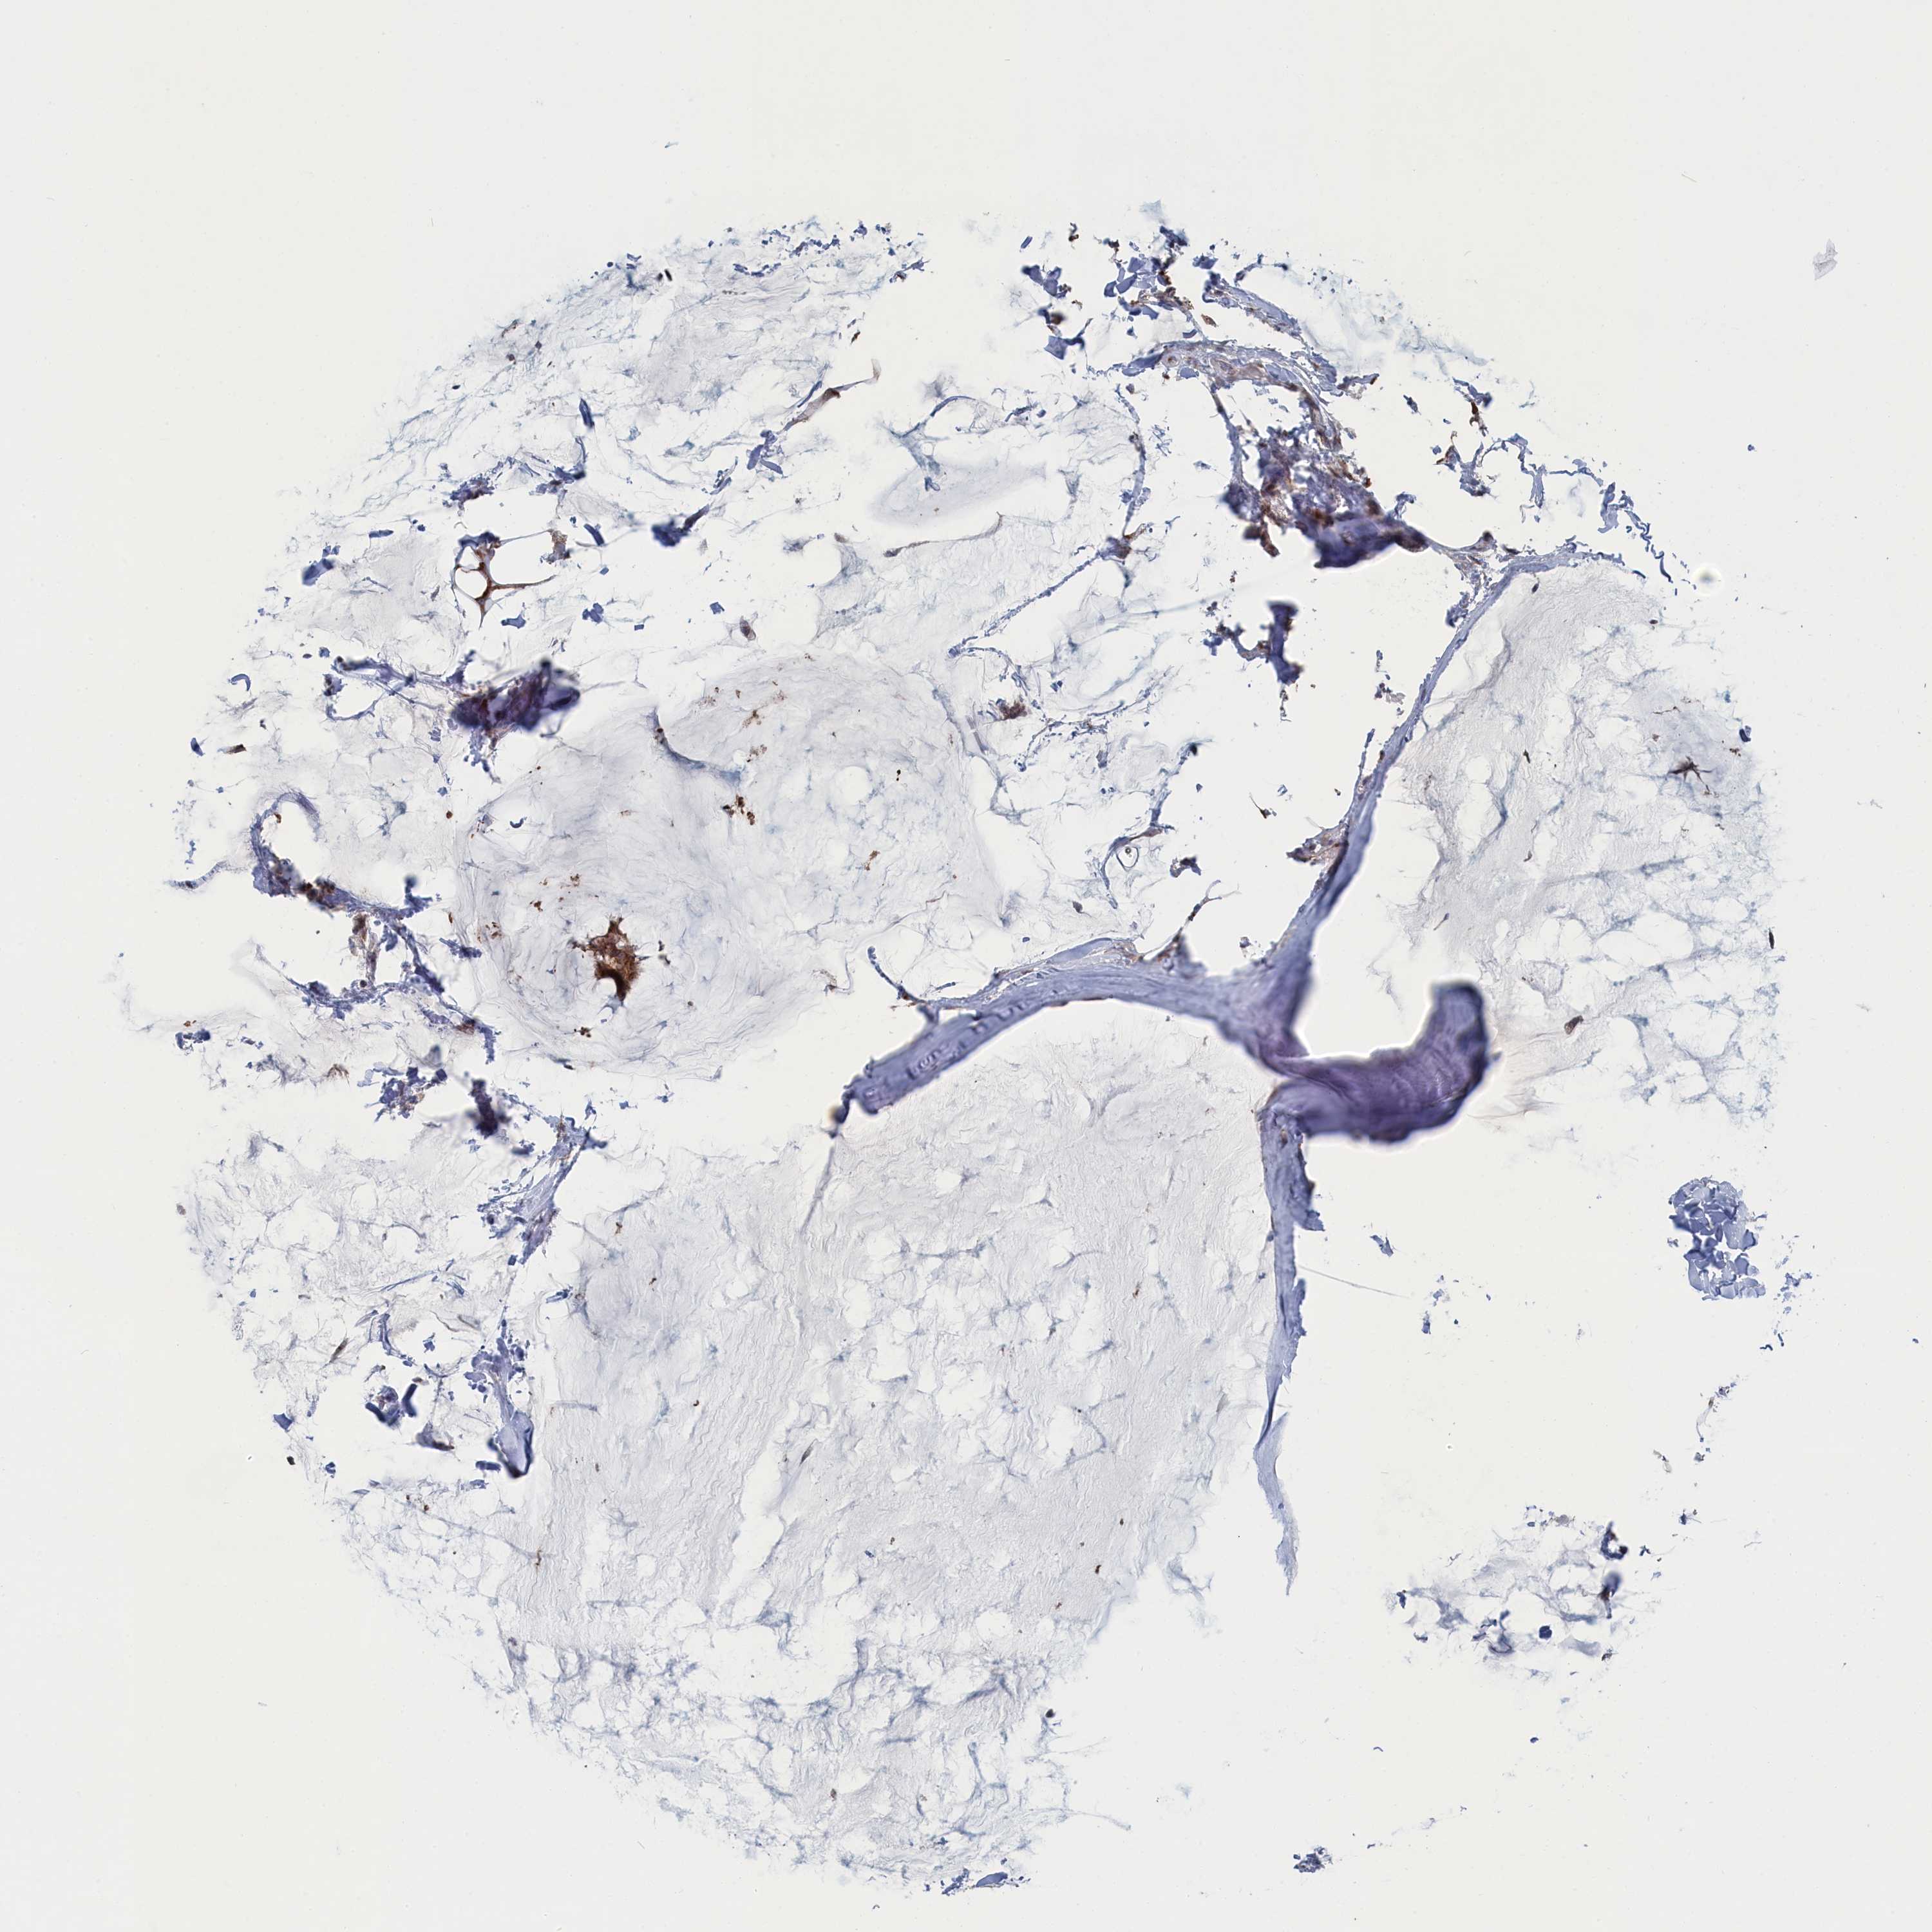

Breast cancer

Human cancer